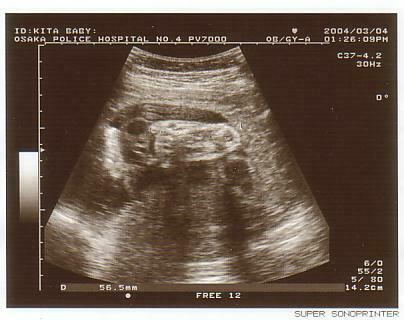

<最終超音波検査>

この日は私も会社を休んで検査について行きました。胎児の臓

器がちゃんとできてるかとか、そういった細かな検査だったの

です。ちゃんとビデオも撮ってきました。

さて、妊娠9ヶ月に入ってますので、家内のお腹は横綱状態。

俊介もお腹の中で「しゃっくり」をしたりと、かなり活発に動

いていました。

私もお腹に手を当てて、ポンポンとたたいてやると、そこで俊

介が動いたりするので、かなり感動したのを覚えています。

3月4日が検査の日だったのですが、この5日後に不覚にも家

内が発熱。夜の9時から警察病院に救急でかかりました。イン

フルエンザではなく、ただの風邪でした。一安心。

この写真は俊介の左足です。